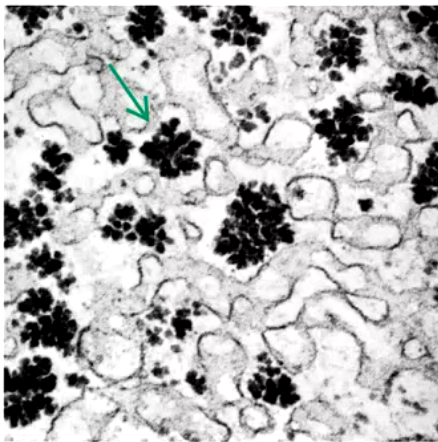

what’s being demonstrated?

G6PDH deficinecy (“Heniz bodies” form in RBC when cells exposed to oxidizing chemical in vitro

precepitiation of hemoglobin occurs due to disulfide bond formation between Hb molecules